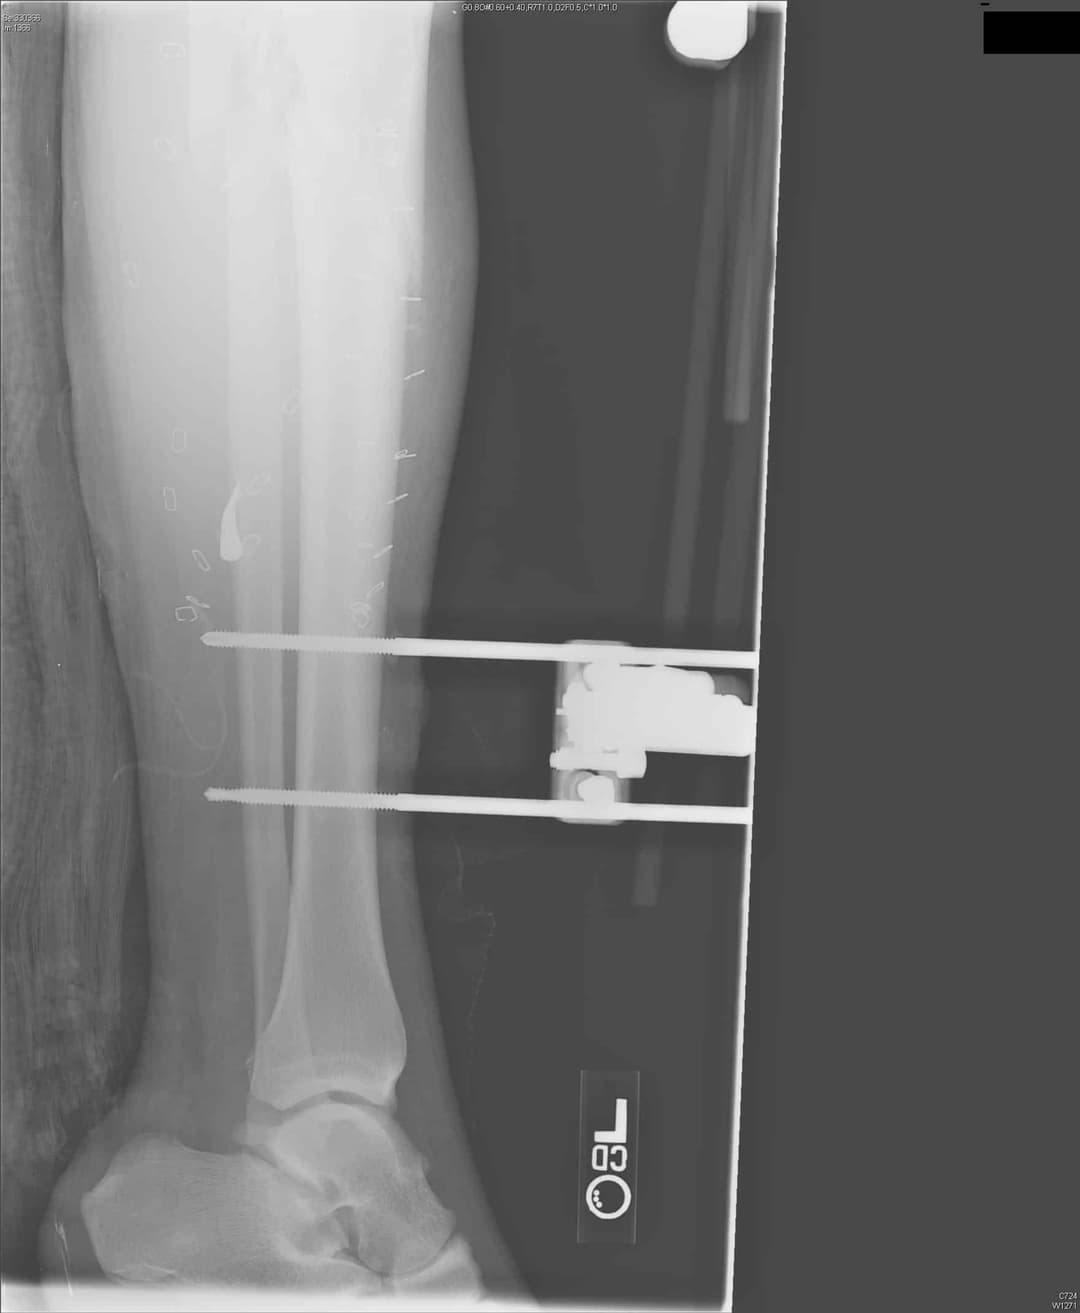

1. див. зобр. 8. Переднезадня рентгенограма встановлення зовнішнього фіксатора з приводу перелому великогомілкової кістки.

Зобр. 8